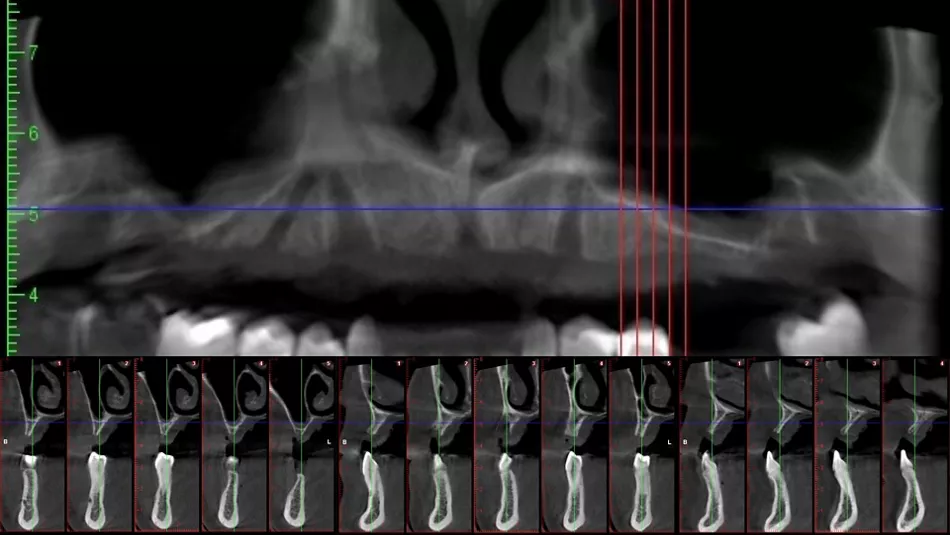

Additionally, the radiographic examination confirmed recent implant loss and demonstrated a critical deficiency of bone in both vertical and horizontal dimensions (Fig. 5). This imaging underscores the necessity for thorough evaluation and intervention to address the underlying bone deficiencies, highlighting the urgent need for a comprehensive treatment plan to effectively restore both function and esthetics.

Fig. 5

At the six-month follow-up, a CBCT scan revealed that the augmented bone had fully integrated, providing the necessary dimensions and stability for implant placement (Fig. 10). Using digital planning software, the 3D positioning of the implants was meticulously planned to ensure optimal placement (Fig. 11). This meticulous planning ensures accurate angulation and depth of the implants, significantly improving both functional performance and esthetic outcome of the final prosthesis.